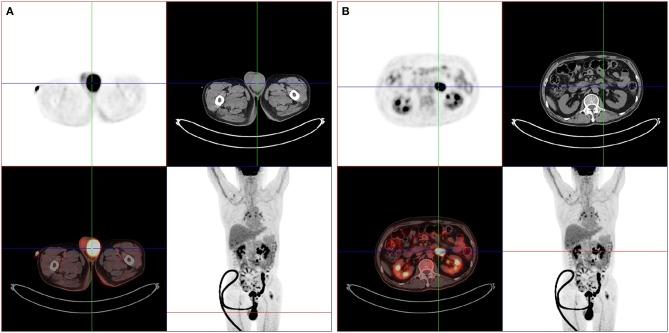

Identifying lymphoma as the cause of neurological disease is diagnostically challenging when the clinical manifestations are atypical. We report an unusual case of a previously healthy immunocompetent 67-years-old man presenting with acute onset of symptoms of myelopathy and mild personality changes. Magnetic resonance imaging (MRI) revealed multifocal periventricular lesions and longitudinally extensive transverse myelitis (LETM). He had very good response to corticosteroids and was in remission for over 6 months. Repeat MRI showed an unexpected mass lesion in the brain which was later confirmed by brain biopsy as diffuse large B cell lymphoma. Subsequent FDG-PET/CT revealed systemic disease with lymphonodal and testicular manifestations (Stage IV disease). It is therefore important to consider lymphoma as a differential diagnosis in patients with LETM and demyelinating lesions in the brain.

当临床表现不典型时,将淋巴瘤确定为神经疾病的病因在诊断上具有挑战性。我们报告了一例不寻常的病例,一名67岁既往健康的免疫功能正常男性,急性起病,出现脊髓病症状和轻度人格改变。磁共振成像(MRI)显示多灶性脑室周围病变和纵向广泛横贯性脊髓炎(LETM)。他对皮质类固醇反应良好,缓解超过6个月。复查MRI显示脑部意外出现肿块病变,后来经脑活检证实为弥漫性大B细胞淋巴瘤。随后的氟代脱氧葡萄糖正电子发射断层扫描/计算机断层扫描(FDG-PET/CT)显示存在系统性疾病,伴有淋巴结和睾丸表现(IV期疾病)。因此,对于患有LETM和脑部脱髓鞘病变的患者,将淋巴瘤作为鉴别诊断是很重要的。